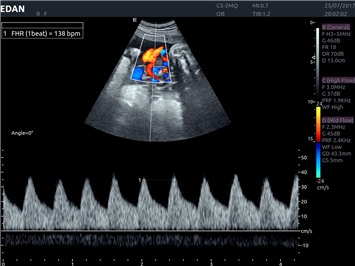

EDAN Acclarix LX4 представляет собой инновационную ультразвуковую систему, построенную на усовершенствованной платформе Acclarix. Сочетание высокого качества визуализации с интеллектуальным рабочим процессом делает эту систему оптимальным выбором для клиник, ценящих эффективность и экономичность.

Цветовой допплер:

Да

Импульсно-волновой допплер:

Постоянно-волновой допплер: